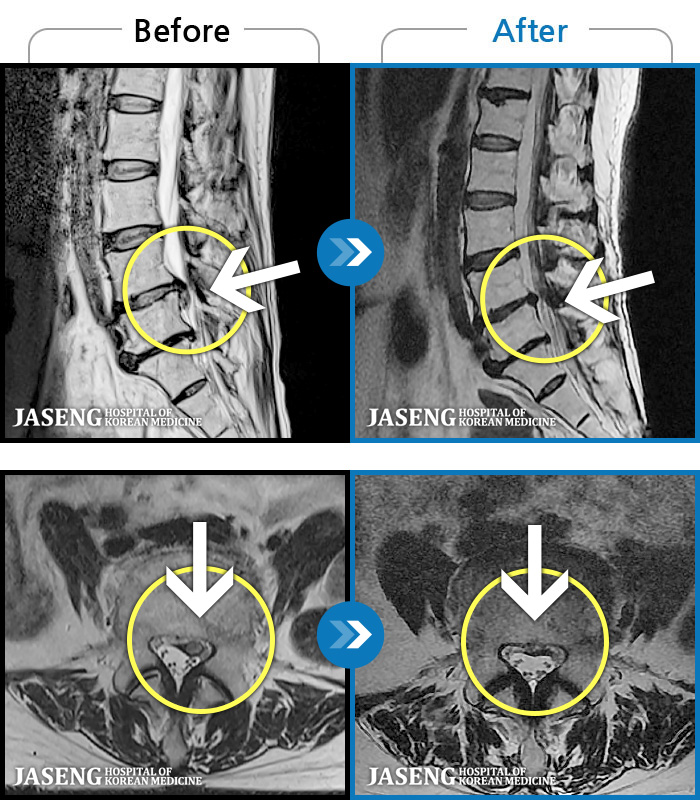

[뱸] 19.11.28~25.05.06